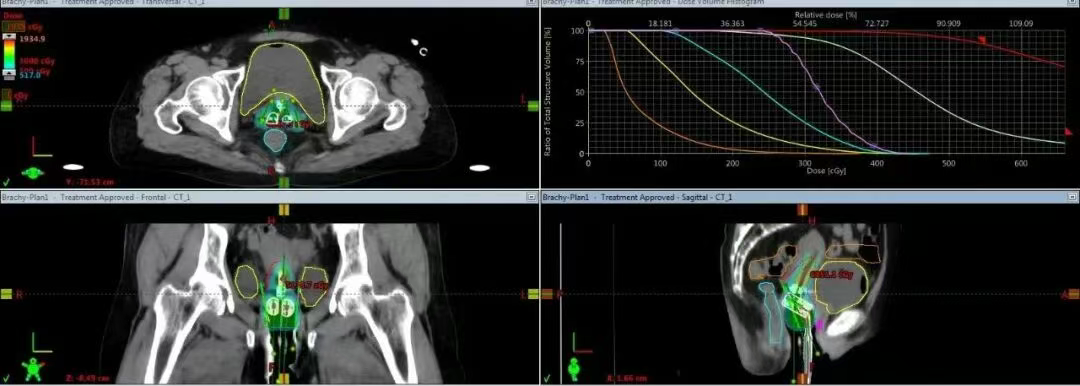

2. 三维设计,剂量“雕刻”

三维后装可根据肿瘤的形态调整照射范围,在提高肿瘤照射的同时大大減低正常组织的照射。实现了靶区剂量的个体化分布,提高了靶区覆盖率,提高了患者生存率,显著降低复发率。基于高清的MRI三维图像,我们可以直接在计算机上进行三维靶区勾画和剂量学优化。物理师精确设计放射源的驻留位置和时间,让高剂量区完美包裹肿瘤(靶区),同时让危及器官的剂量曲线急剧跌落。

患者在特定的施源器放置后,进入CT及MRI室进行扫描。影像即刻传输至治疗计划系统,融合CT及MRI图像后医生勾画靶区与危及器官,物理师进行快速、精准的剂量计算与优化,验证审核无误后即刻实施治疗。